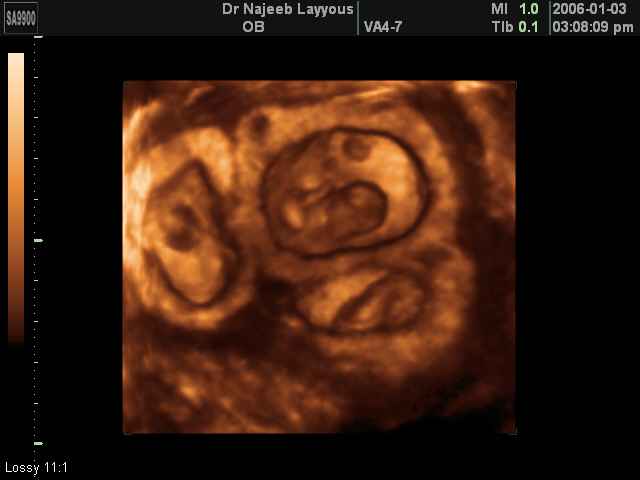

- صور لتوائم

صور لتوائم بجهاز الالتراساوند ثلاثي الأبعاد | الدكتور نجيب ليوس